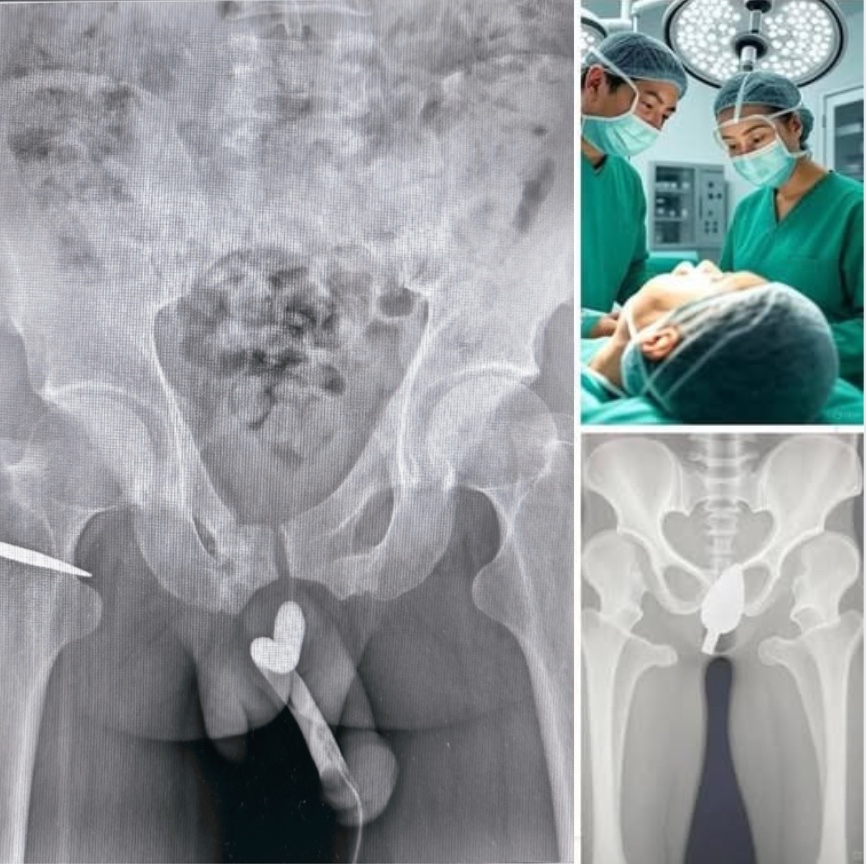

A shocking incident has recently surfaced online and in health forums, sparking widespread concern and debate about the risks teenagers sometimes take without fully grasping the consequences. A teenage girl was hospitalized after attempting a dangerous and misguided experiment involving a household item. According to reports, she inserted a pen into her body, which led to severe internal injuries and complications that required urgent medical attention.

Doctors at the hospital where the girl was treated reported that her condition was critical upon arrival. The pen had caused internal damage that led to heavy bleeding and a risk of infection. She was rushed into emergency surgery, and medical professionals worked tirelessly to stabilize her. The incident serves as a sobering reminder of just how fragile the human body can be when subjected to careless or reckless actions. Thankfully, early reports indicate that she is now recovering, but the road to full healing—both physically and emotionally—will be long.